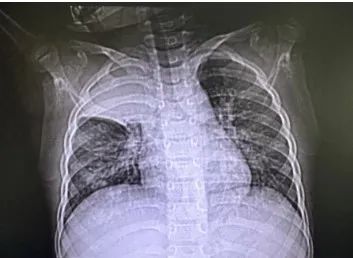

记者了解到,该患儿入院前三天突发咳喘,出现发热后前往上海市儿童医院呼吸科就诊。呼吸专科门诊医生胸片检查发现两肺纹理增多,右上肺高密度影,可能存在感染性病变;随即被收治入呼吸科病房。入院后患儿血氧饱和度最低仅89%,出现呼吸衰竭,紧急肺部CT检查发现右肺上叶影像完全消失,右肺少量胸腔积液。

患儿术前的影像